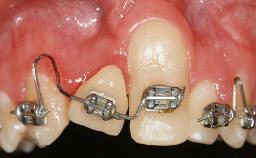

Treatment of Soft-Tissue Fenestration in the Esthetic Zone

This case demonstrates that a connective-tissue graft in combination with a coronally positioned graft is an effective method of treating cases with peri-implant mucositis and an abutment-level sinus abscess. A 42-year-old man presented with a swelling adjacent to an implant crown at site 21. The swelling had been present for approximately three weeks and was constrained to the buccal and palatal gingival aspects of the implant. A discharge was noted on finger pressure, with localized gingival recession present on the mid- and distolabial aspects of the crown.